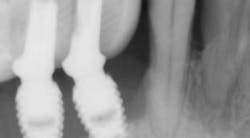

Recently, a regenerative surgical protocol that uses both mechanical and chemical means for implant surface detoxification—together with a bone graft and/or substitute including coverage with a barrier membrane and a two- to 10-year follow-up period—has been shown to have a 98.8% implant survival rate. The results of this study were based on peri-implantitis treatment of 170 consecutive dental implants in 100 patients. (13) In that specific study, an air powder abrasive was utilized as part of the surface decontamination.